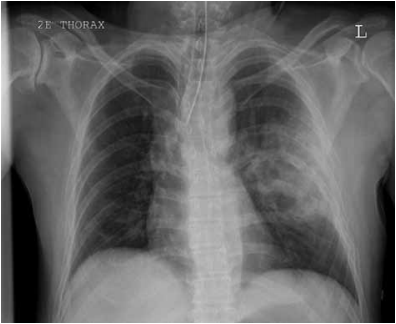

Paciente de 18 anos, vítima de trauma, apresenta o r-X ilustrado a seguir.

Nesse momento, é recomendável